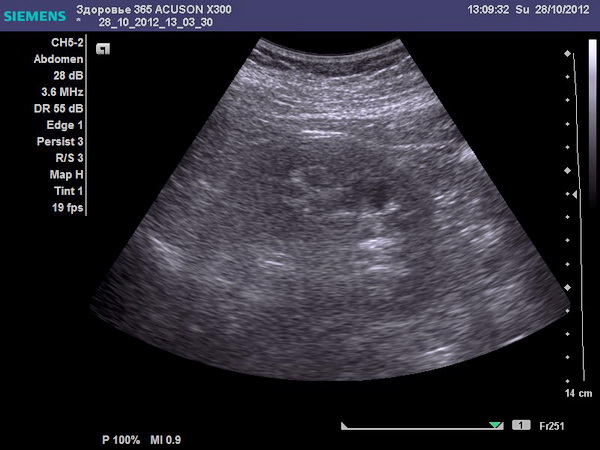

- УЗИ;

Ультразвуковое исследование

Если вы хотите узнать, что показывает УЗИ позвоночника, а также его особенности и преимущества, прочитайте статью на нашем портале.

- УЗИ — показывает наличие камней в почках и изменения в органах малого таза и ЖКТ.